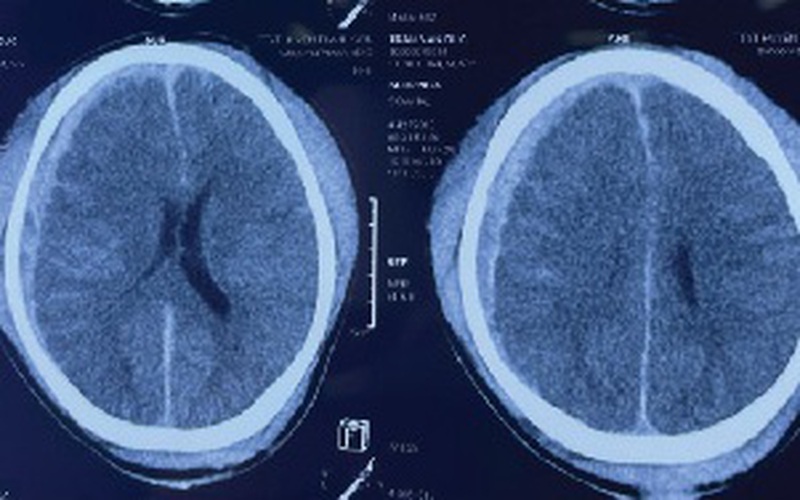

Các bác sĩ Khoa Ngoại yêu cầu – Bệnh viện đa khoa tỉnh Phú Thọ vừa hội chẩn cho một bệnh nhân bị chấn thương sọ não nặng do ngã cao khi đang lao động, cụ thể là 1 thợ xây trong quá trình làm việc bị ngã ở độ cao khoảng 3 mét nhưng do không có bảo hộ lao động đã bị chấn thương sọ não phức tạp (vỡ xương sọ phức tạp và chảy máu trong não).

Mặc dù đã được đưa đi cấp cứu kịp thời nhưng bệnh cảnh lâm sàng quá nặng, bệnh nhân không có chỉ định can thiệp phẫu thuật.